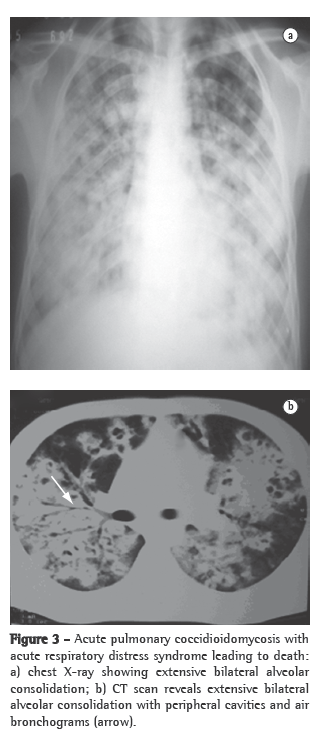

Primary pulmonary coccidioidomycosisThe most common form of presentation of coccidioidomycosis, primary pulmonary coccidioidomycosis is characterized by pulmonary manifestations that generally appear one to three weeks after exposure to the fungus. Approximately 60% of the infected individuals evolve to spontaneous cure without clinical or radiological manifestations. The remaining 40% generally present symptoms of acute respiratory disease, mimicking the flu, accompanied by fever, night sweats and cough or pleuritic chest pain, or a combination of the two. The manifestations appear between 10 and 15 days after exposure to the fungus, and the intensity of the symptoms depends directly on the infective load, ranging from the flu to a severe, nonspecific respiratory infection, accompanied by high fever, chest pain and cough with or without expectoration, as well as by general symptoms or allergic manifestations, particularly erythema nodosum. Primary pulmonary coccidioidomycosis generally resolves spontaneously within 30-60 days, even without antifungal treatment. However, approximately 5% of these patients develop residual pulmonary lesions (generally solitary nodules) that are asymptomatic in most patients. These cases are often diagnosed after surgical removal due to suspected lung cancer. Another 5% of these patients develop thin-walled cavities, solitary and juxtapleural, that might resolve spontaneously in approximately 2 years. In certain cases, principally in diabetic or immunocompromised patients, the acute pulmonary form does not resolve; it progresses to chronic pneumonia and is characterized by the formation of pulmonary cavitation. The lungs might also be diffusely affected as a result of the inhalation of a large quantity of infective arthroconidia or as a late and secondary presentation resulting from hematogenous dissemination. These forms present with multiple diffuse infiltrates, the largest of which might present cavitation accompanied by severe respiratory manifestations, which can lead to respiratory failure and are more commonly observed in immunocompromised patients. The disease might progress to death, mimicking septic shock, accompanied by acute respiratory distress syndrome, with high mortality rates.(13,27)

Other testsNonspecific tests that are useful for the evaluation of patients include X-rays and CT scans of the affected site, principally of the chest, and can greatly aid in the diagnosis (Figures 2 and 3). The most common findings on chest X-rays are multiple lung nodules of peripheral distribution, associated with parenchymal consolidation. CT scans of the chest reveal peripheral lung nodules that are predominantly cavitated.(29,39)